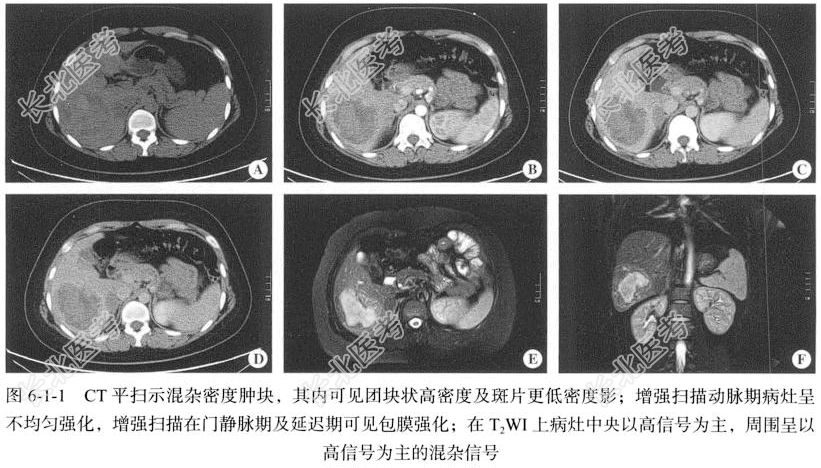

【腹部CT检查】仰卧位,横断位扫描,CT扫描采用美国GE Discovery 750HD能谱CT扫描仪,行上腹部定位平扫及双期增强扫描。层厚设定为5.00mm,层间距设定为5.00mm,重建间隔设定为2.50~5.00mm,螺距设定为0.50~1.50,最大管电压均为120kV,最大管电流均设定为200~260mA。增强扫描时对比剂采用碘伏醇(含碘320mg/ml),以3.5ml/s的流率注射1.5ml/kg,注射完成后以相同流率注射20ml生理盐水。分别延迟20~25秒、45~55秒行动脉期、门静脉期扫描。

【影像图片】见图6-1-1。